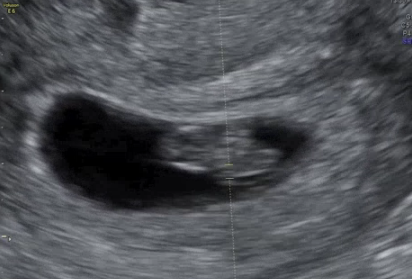

첫째는 건강했지만, 둘째는 태어날 때부터 저체중으로 인큐베이터에 들어갔고,

셋째는 정밀 초음파에서 선천성 질환 가능성 때문에 추가 검사를 받았던 기억도 있어요.